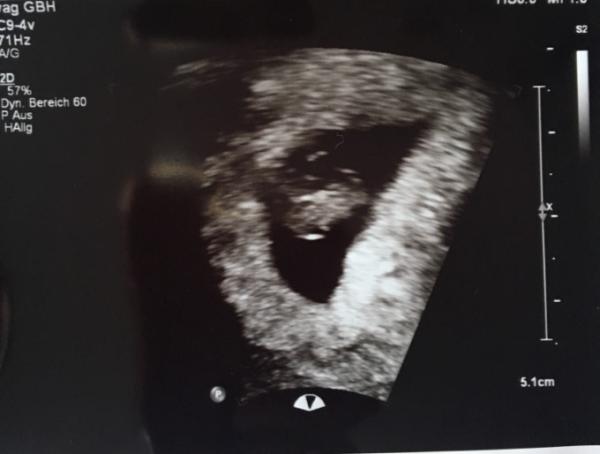

Hallo ihr Lieben! Ich habe bisher nur still mitgelesen,nun habe ich schon so viel über MA gelesen dass ichs nun mit der Angst zu tun kriege.Mein letzter US war 7+2 da war alles super und laut Sono eher 7+5. Mein nächster Termin ist erst am 18. bei 10+1...hab jetzt total dolle Angst keinen Herzschlag mehr zu sehen obwohl ich mich schon so sicher gefühlt habe Wie kriege ich denn nun die Zeit bis dahin rum???KH ist für mich keine Option und meine Gyn will ich eigentlich auch nicht nerven nur weil ich durch so Berichte Angst gekriegt habe:( Sorry für den langen text und das Gejammer!! Liebe Grüße und schöne Pfingsten allen!

Hi, Ich habe bisher auch nur still mitgelesen aber du hast mir gerade so aus dem Herzen gesprochen dass ich dir einfach unbedingt antworten wollte Mir gehts gerade genauso wie dir. Ich war bei 7+4 beim FA und da sah alle super aus: Herzschlag, Größe etc alles genauso wies sein sollte Meinen nächsten Termin habe ich am 17. bei 11+3 und sehe der ganzen Sache mit gemischten Gefühlen entgegen. Ich hatte letztes Jahr im November eine Fehlgeburt bei 6+5 und seit dem habe ich das Vertrauen etwas verloren. Vor meinem ersten Termin beim FA war ich kurz davor ihn einfach abzusagen. Ich wollte gar keine Gewissheit haben über diese SS.. ich wollte einfach noch weiter die Hoffnung haben, dass es dieses Mal klappen könnte. Mit dem neuen Termin ist es genauso. Einerseits kann ich’s kaum erwarten dass die Ärztin wieder sagt dass alles super ist und andererseits hab ich heftig Angst davor dass mir wieder der Boden unter den Füßen weggezogen wird. Das letzte mal bin ich in ein so tiefes Loch gefallen, deshalb haben mein Mann und ich so lange gewartet mit einem neuen Versuch, einfach weil ich den Gedanken dass es wieder ein Sternchen werden könnte kaum ertragen kann. Ich bin ein absoluter Kopfmensch ich muss immer alles ganz genau wissen. Etwas nicht zu wissen oder zu verstehen macht mich wahnsinnig. Deshalb hab ich, wie du, alles gelesen was ich über Fehlgeburten gefunden habe. Ich habe, wie du, im Moment total Angst vor einem MA. Das letzte mal bin ich zum Glück um eine Ausschabung herum gekommen, aber jetzt bin ich ja deutlich weiter.. wer weiß ob ich danach nochmal den Mut für einen neuen Versuch finden kann? Sorry für die lange Antwort! Was ich eigentlich sagen will: du bist nicht allein und jetzt versuchen wir und einfach nicht verrückt zu machen! Noch eine Woche, dann wissen wir mehr! Fühl dich unbekannterweise gedrückt